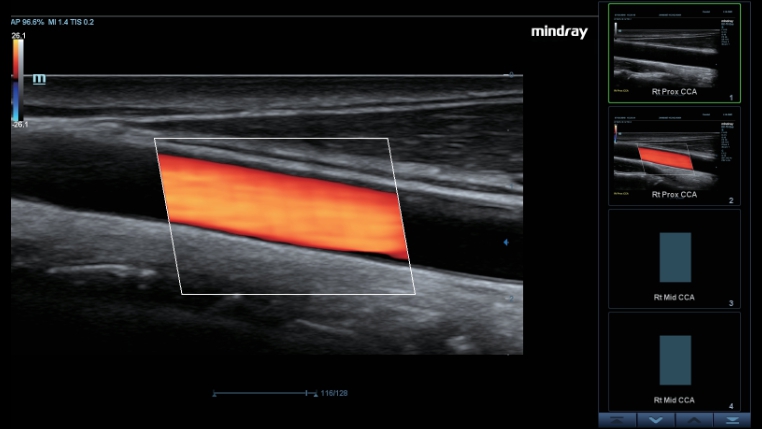

Transductores ComboWave

En comparaciĂłn con los sensores tradicionales, los transductores ComboWave utilizan un nuevo tipo de material piezoelĂ©ctrico compuesto que optimiza notablemente el espectro acĂșstico y reduce la impedancia acĂșstica. AdemĂĄs de integrarse con la tecnologĂa Ășnica 3T de Mindray, los transductores lineales ComboWave ofrecen un rendimiento sobresaliente con una gran uniformidad y resoluciĂłn de imagen en ecografĂas vasculares, de tiroides, de mama, etc.

Smart Track

Smart Track proporciona una optimizaciĂłn rĂĄpida e inteligente de imĂĄgenes vasculares con un sencillo manejo de un solo toque. Puede optimizar el espectro de Color, Potencia y PW mediante seguimiento automĂĄtico y reducir los pasos que llevan tiempo. Por lo tanto, el flujo de trabajo del examen vascular se simplifica con una Ăłptima visualizaciĂłn.